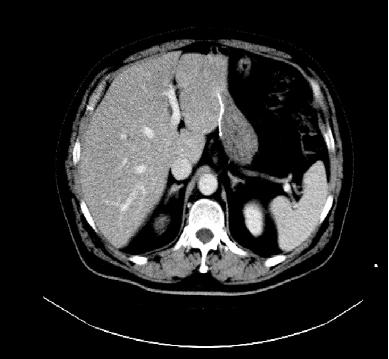

胸腹盆增强CT(2020-05-08):直肠癌治疗术后,左下腹造瘘术后,肝脏多发转移较前增多增大,双肺气肿,主动脉及冠状动脉硬化,双肾囊肿

诊断:直肠腺癌术后,转移(肝)。